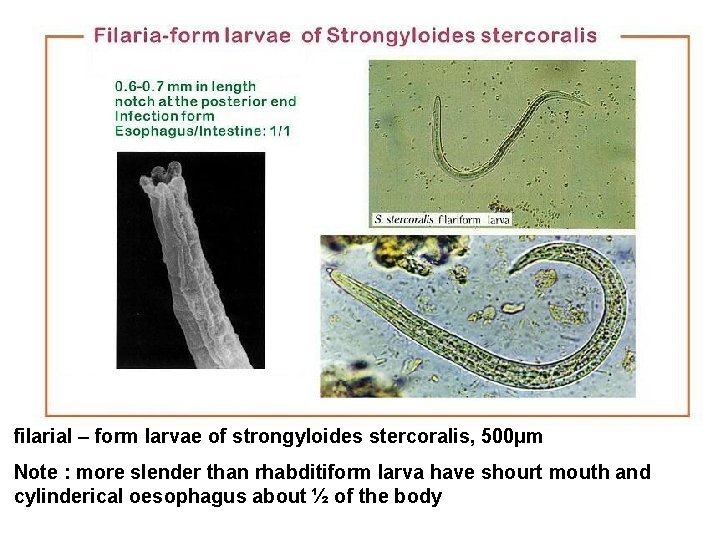

filarial – form larvae of strongyloides stercoralis, 500µm Note : more slender than rhabditiform larva have shourt mouth and cylinderical oesophagus about ½ of the body